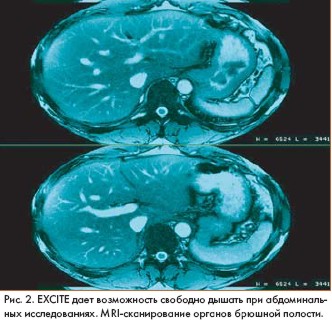

Магнитно-резонансные изображения (magnetic resonance imaging - MRI), полученные на основе высокоскоростного сканирования с помощью технологии GE Excite, открывают новые возможности хорошо известного метода исследования. Идея была представлена на 10-й научной конференции Международного общества Magnetic Resonance in Medicine, которая прошла в США.

Система GE Excite была разработана компанией GE Medical Systems (США). Высокая скорость сканирования и компьютерной обработки данных позволяет получать объемные MR-изображения высокого разрешения в реальном времени, например в процессе работы сердца.

"Мы впервые получили возможность получать изображения в процессе реальной жизнедеятельности органов, - говорит доктор Lawrence Tanenbaum из Института неврологии Нью Джерси (США). - GE Excite не требует задержки дыхания в процессе исследования больных и особенно удобна для получения качественных изображений органов, находящихся в движении, например сердца и сосудистой системы"

Представители GE Medical Systems заявляют, что новая технология позволит врачам улучшить качество и информативность диагностики заболеваний сердца, последствий инсульта, желудочно-кишечной патологии, ортопедических нарушений.